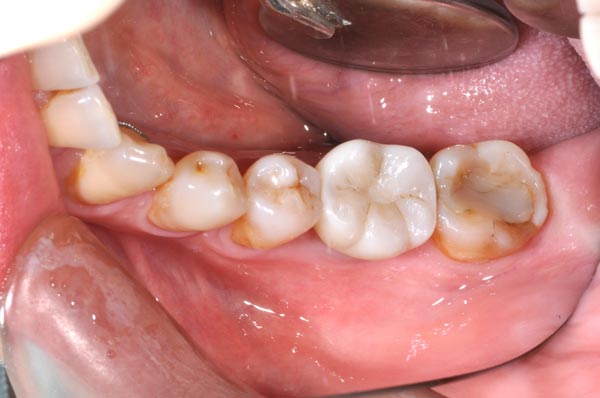

植牙前

植牙全瓷牙冠

植牙後

更多植牙案例